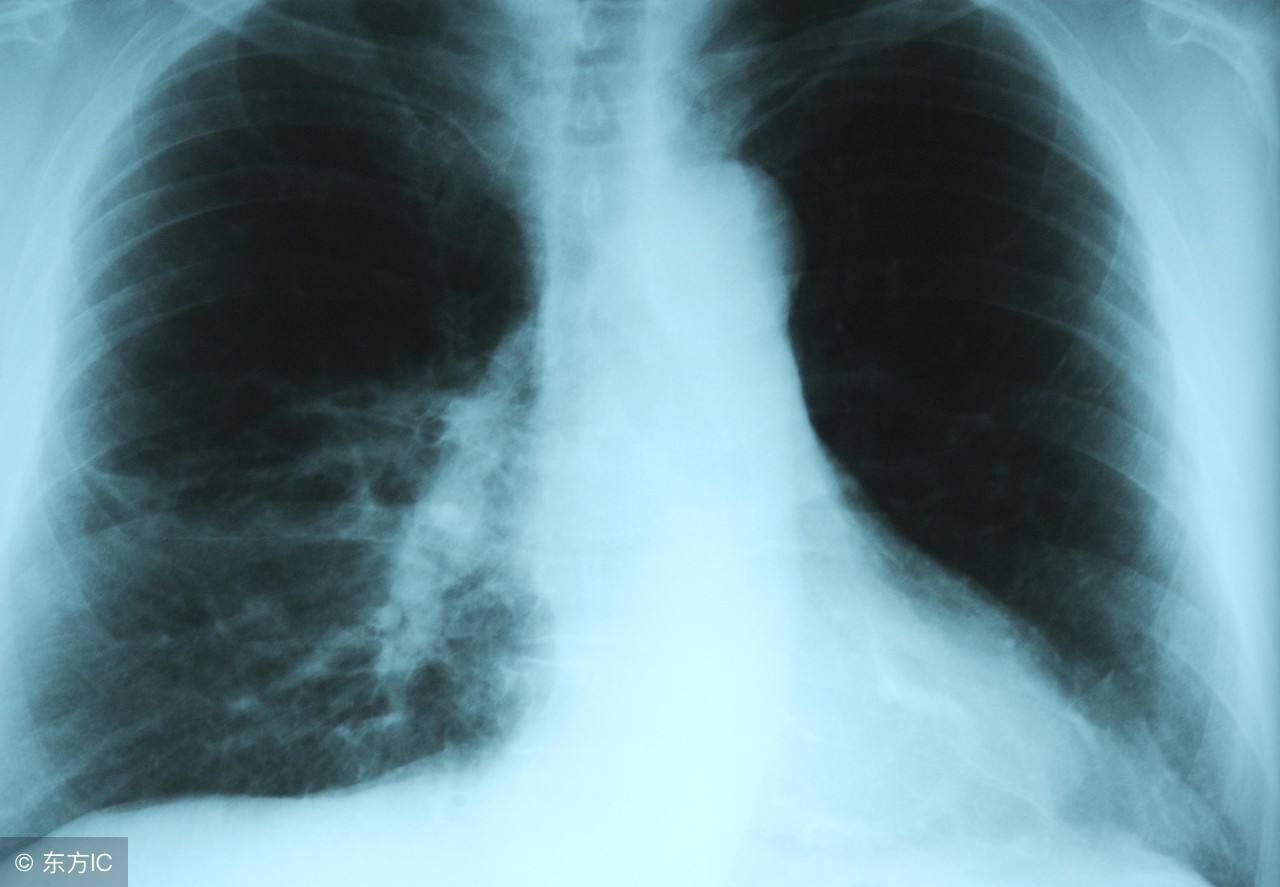

肺炎疾病是人们生活中常见而不陌生的了。要是人们患上肺炎疾病的刹那是很担心的,肺炎患者的饮食是会受限制的。不同的致病原可引起不同类型的肺炎。那么,如何鉴定宝宝得了肺炎呢?